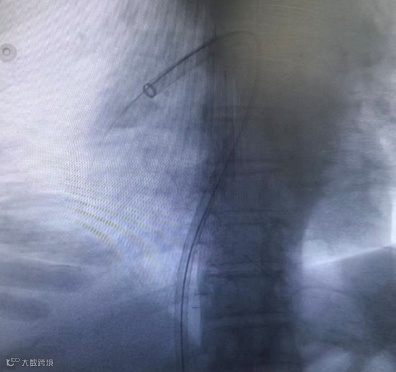

右侧股静脉置管,送⼊ 5F Pigtail 造影导管⾏双肺动脉造影。右下肺动脉主干及多肺段均见充盈缺损 ,部分分支闭塞。左肺主干及多肺段均见充盈缺损。

术前造影